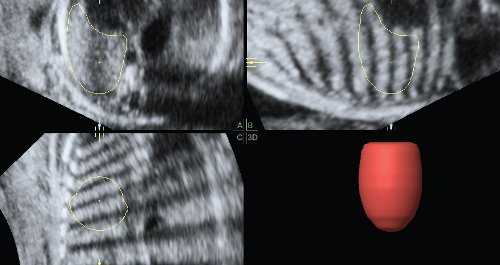

На первый взгляд, эта методика не очень сложна, однако правильно провести все этапы объемной реконструкции можно только при высоком качестве первично полученного объема. Даже при отсутствии патологии легких существует много факторов, затрудняющих визуализацию этого органа и влияющих на качество объемной информации. Прежде всего это срок беременности. До 32 нед неудачными для дальнейшей обработки являются 3-7% от всех сохраненных объемов, тогда как после этого срока - около 30%. Кроме того, к таким факторам относятся маловодие, плохая визуализация плода при ожирении пациентки, неудобное (например, поперечное) положение плода. Диафрагмальная грыжа сама по себе резко ухудшает визуализацию легких в связи с их компрессией (рис. 2) [3].

Рис. 2. Измерение объема контралатерального легкого при левосторонней диафрагмальной грыже. Тень от ребер мешает визуализации границ компрессированного легкого.